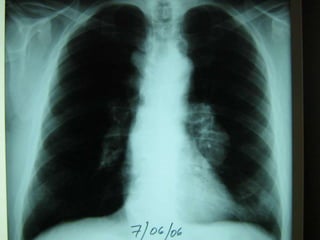

•   Ganglios linfáticos cervicales

inferiores, supraclaviculares y